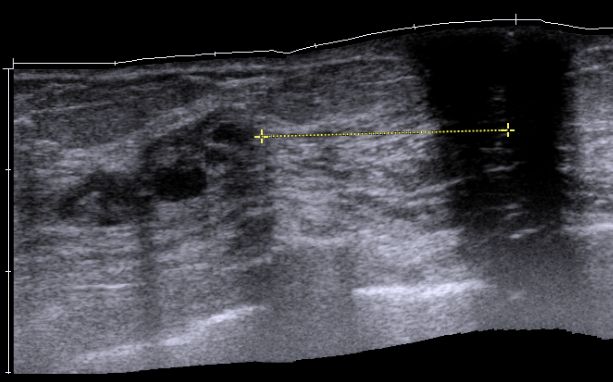

| Mammographie | 76-jährige Patientin mit multiplen Metastasen in Wirbelsäule und Leber. Zunächst kein Tastbefund der Brust. Dann suspekter Tastbefund rechts oben außen paramamillär. Mammographie zunächst o.B. befundet. Stanzbiopsie rechts oben außen: lobuläres Karzinom. | |||||||||